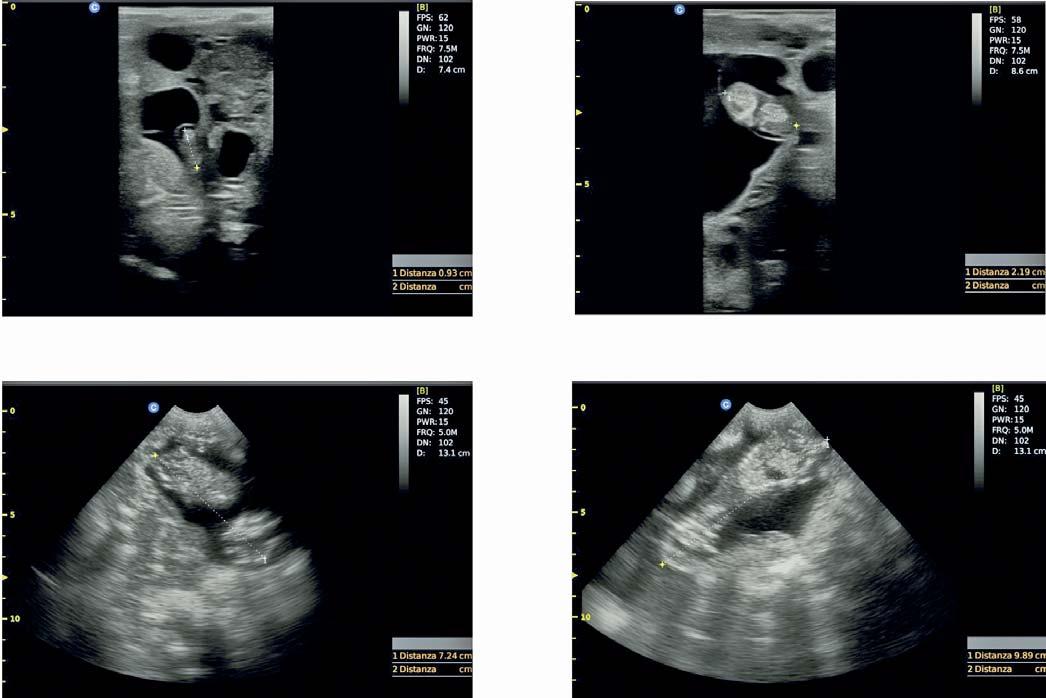

Measures of foetal growth during gestation have been published for several goat and sheep breeds to calculate the estimated gestational stage. Up to date, no study is available in the literature for the Sarda sheep. The aim of this study was to investigate, by ultrasonography, the foetal and placental morphometry in the Sarda sheep. A total of 256 ultrasonographic images were achieved from six ewes from day 24 of pregnancy (D24) to D92. The crown to rump length in cm (CRL) was recorded and, using visual scales score, foetal ossification (1 = absence; 2 = a few; 3 = several ossifications) and development of placental cotyledons (1 = absence; 2 = visible but immature; 3 = mature) were categorised. The data regarding CRL were analysed using a MIXED procedure while aspects of ossification and cotyledons using the Fisher’s exact test. The effect of the pregnancy stage on CRL was statistically significant (p < 0.001) and all the stages were differentiable each other. The least squares means of CRL spanned from 1.33 (D24 to D30) to 9.85 cm (D55 to D60). The effects of parity and lambing rate on CRL were not significant and the total variance attributable to the random effect of the single sheep was negligible. Based on the aspect of both ossification and cot yledons, it was possible to differentiate pregnancy stages between D31 to D50. These results are useful for veterinarians, in the field of reproductive management of Sarda sheep farms, to provide a consistent prediction of the date of lambing.

Ultrasonographic examination to manage reproduction and pregnancy diagnosis in small ruminants farming is well recognized 6. In meat sheep farming and productions, ultrasound diagnosis has improved the flock management, and the procedure is also performed to predict sheep carcass performances 5,7. Nevertheless, the method is now an essential part of health planning and farm productivity, mainly for reproductive improvement and pregnancy diagnosis as highlighted by Scott 5 and Meinecke-Tillmann 8. Also, field veterinarians in the sector of dairy sheep farming are often asked to predict breeding and reproductive potential of rams 9,10, pregnancy stage and lambing date of sheep when oestrus and breeding dates are unknown. This allows to cull unproductive animals, get an early lambing, a longer season of milk production and finally a better farm management 11-13. Moreover, information about

pregnancy and stage of pregnancy allow to optimize pharmacological treatments, avoiding teratogenic molecules, and the efficacy of vaccine prophylaxis 11-13

In the sector of dairy sheep, the countries of Southern Europe are the leading in terms of heads, productions and economic profit 14. Sardinia is an insular region of Italy in the middle of the Mediterranean Sea where about 3 million dairy sheep are reared using the semi-extensive methods 15 and the local breed, the Sarda. The Sarda is the most common dairy sheep breed in Italy with 180,000 animals and 700 herds officially recorded in the flock book 16 and it is also appreciated in North African and East European countries 15. Measures of foetal growth during gestation have been published for small ruminant species, from several goat and sheep breeds to calculate, via predictive equations, the estimated gestational stage 3. Up to date, no study is available in the literature relating to a precise morphometric assessment of the foetal staging in the Sarda sheep. The aim of this preliminary study is to investigate, by means of ultrasonography and the resultant on-field traits, the embryonal and foetal (foetal from this point), and placental morphometry in the Sarda sheep and provide a suitable tool to predict pregnancy stages.